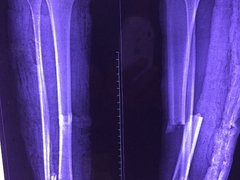

Khớp gối có thể bị hủy hoại vì chạy để giảm cân

Nguyễn Văn Thạch, Chủ tịch Hội Chấn thương Chỉnh hình Việt Nam, đã chia sẻ như vậy bên lề Hội nghị Chấn thương Chỉnh hình Đông Nam Á, diễn ra tại Hà Nội từ ngày 6 đến 8-10.